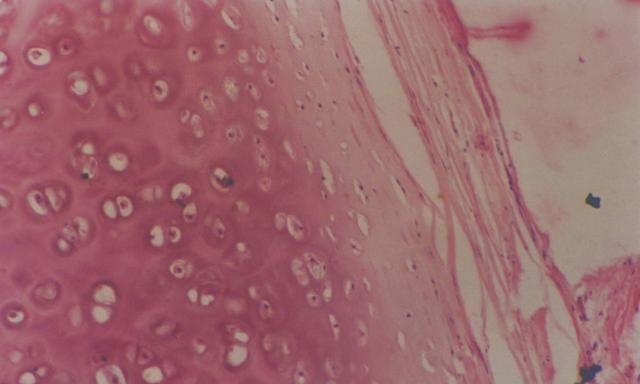

骨头“散架”是怎么回事呢?“散架”的骨头其实是软骨,就是你耳朵或者鼻子上的那种骨头。

虽然婴儿有300多块骨头,但其中只有170多块是真骨,其余的都是软骨,婴儿比成人多出来的骨头正是软骨。

软骨是一种类似橡胶,光滑、有弹性的结缔组织,既不像骨头那么坚硬,又不像肌肉那么柔软。

而且在融合的同时,软骨也在慢慢变硬变成骨头,这个过程又叫做软骨内骨化,是包括人在内的哺乳动物胎儿产生骨组织的一个重要过程。